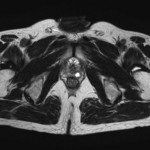

[画像診断]前立腺・傍前立腺嚢胞性疾患について 2010-08-14